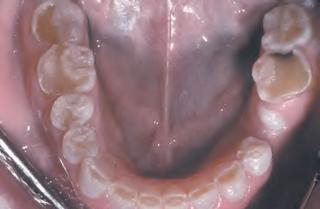

Odontoma | compound | 最常見 | 上顎前牙 | 20y ↓ |

![]() ![]() |

|

complex | 後牙 |

||||